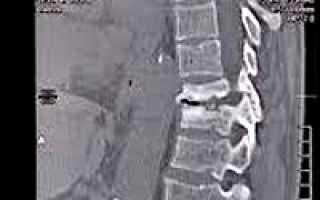

Дифференциальную диагностику туберкулёза позвоночника у детей проводят с неспецифическими воспалительными поражениями, врождёнными пороками развития позвонков, дегенеративными и опухолевыми процессами. Для них характерен низкий уровень специфической аллергии по данным туберкулиновых проб, серологической и иммунологической диагностики.

• Для хронического гематогенного остеомиелита позвоночника типичен подростковый возраст больных, в анамнезе — острое начало заболевания с выраженным болевым синдромом и температурной реакцией. При лабораторных исследованиях выявляют умеренный лейкоцитоз, повышение СОЭ, диспротеинемию. При рентгенографии обнаруживают менее глубокую, чем при туберкулёзе, контактную деструкцию тел II-III позвонков с остеосклерозом поражённых тел.

• При неспецифических воспалительных процессах в позвоночнике при МРТ выявляют преимущественно изменение межпозвонкового диска (деформацию и исчезновение пульпозного ядра, отёк или дегенерацию диска) с усилением сигнала от тел контактных позвонков.

• Среди пороков развития туберкулёзный спондилит обычно дифференцируют с врождёнными кифозами I типа, вызванными нарушениями формирования тел позвонков. Для аномалий характерно отсутствие анамнестических, клинических и лабораторных признаков воспаления, при лучевом исследовании выявляют нарушение формы позвонков при сохранении их чётких контуров, структуры и отсутствии реакции мягких тканей.

• Среди дегенеративных заболеваний позвоночника у детей наиболее часто туберкулёзный спондилит дифференцируют с ювенильным остеохондрозом, обычно выявляемым в подростковом возрасте. Для дегенеративных процессов характерно отсутствие анамнестических, клинических и лабораторных признаков воспаления. На рентгенограммах, как правило, на значительном протяжении позвоночника выявляются разрыхлённость замыкательных пластинок тел позвонков, изменение их конфигурации, хрящевые узлы и грыжи Шморля.

• Позвоночник. Может страдать как один позвонок, так и несколько. В 60% случаев наблюдается поражение грудного отдела, в 30% – поясничного отдела.

Для подтверждения диагноза назначают рентгенографию грудной клетки, рентгенографию пораженного сегмента и МРТ пораженного сегмента. На снимках грудной клетки больных, страдающих туберкулезом костей, выявляются кальцинированные первичные туберкулезные очаги в верхних отделах легких и внутригрудных лимфатических узлах. На рентгенограммах позвоночника или пораженных костей конечностей видны очаги разрушения и секвестры. В некоторых случаях удается заметить тени натечных абсцессов.